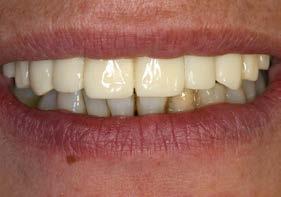

Un año más tarde, al finalizar el periodo de seguimiento (24 años), las fotografías intraorales evidenciaron ligeras alteraciones de los tejidos blandos, con pequeñas troneras abiertas,

más evidentes en los dientes naturales conservados que en las restauraciones implantosoportadas. A pesar de estos cambios, el resultado global se consideró satisfactorio desde el punto de vista funcional y estético, especialmente en comparación con la situación clínica y radiográfica inicial previa al tratamiento (Figuras 26–31).

Figuras 30 y 31. Comparativa inicial y final a los 25 años de seguimiento, que muestra la estabilidad alcanzada tanto en los dientes conservados como en los implantes.